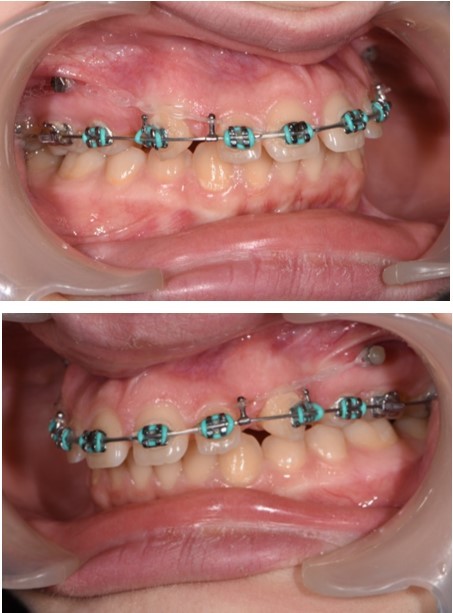

Treatment started with orthodontic appliances on the upper arch, Roth 022" prescription. In order to achieve a better retraction of the upper teeth, first bicuspids were extracted. Retraction of the upper incisors with elastics chains placed from crimpable hooks to orthodontic implants.

The working stage of the treatment was done with the use of a rectangular stainless steel archwire 0.019”x0.025” (Figure 5, Figure 6). Bodily movement was obtained and a minor intrusion. The incisal edges were displaced backward in order to provide a better incisal display at rest and during the smile. Unlike palatal arches, where the retraction is done by tipping the incisors, the mini implants in our case were able to provide a bodily retraction of the upper anterior teeth. Therefore, retraction was obtained with no anchorage loss. The improvement in the overjet and overbite was good.

Figure 5.Retraction of the upper incisors with elastics chains placed from crimpable hooks to orthodontic implants.

Figure 6.Significant overjet and overbite improvement after implant based orthodontic retraction.